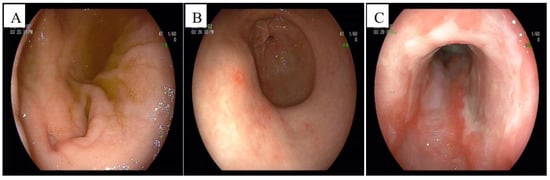

2. Case Presentation